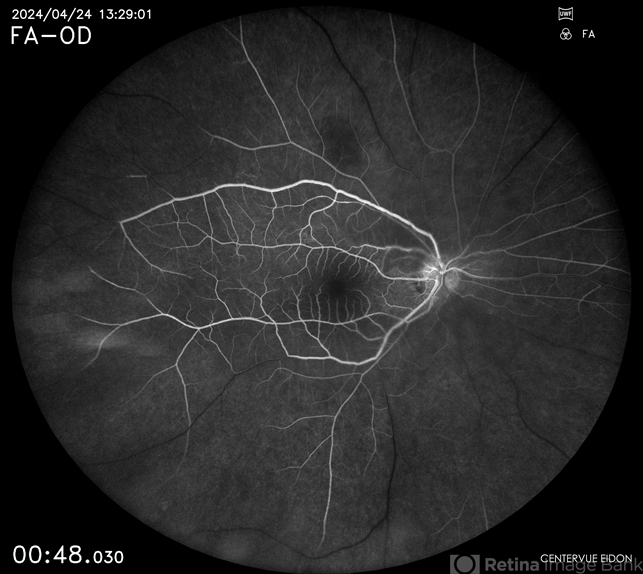

- CRAO, central retinal artery occlusion (CRAO)

- Dr. Akansha Sharma, Bharati Eye Hospital

- Scanning laser ophthalmoscope

- Early phase fluorescein angiography of a 40 year old female with central retinal artery occlusion.